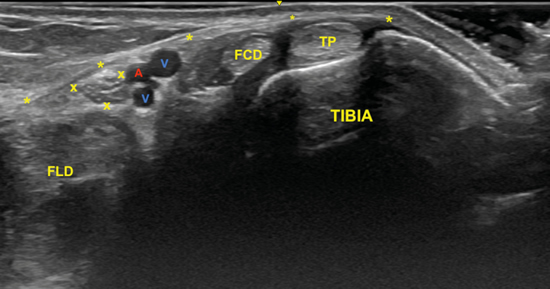

Para realizar la exploración sonográfica, se debe exponer la cara medial del tobillo y el pie. Se ha de comenzar con el examen del nervio tibial en eje corto (plano transverso), situando la sonda en el túnel tibiotalar superior (Figuras 4 y 5)5.

El nervio tibial, que se sitúa en superficie a las estructuras musculotendinosas y bajo la fascia crural, de forma habitual está dispuesto posterior a los vasos tibiales posteriores (Figura 6).

Nervio plantar medial y plantar lateral

El examen para localizar la división del nervio tibial continúa desplazando la sonda en eje transverso y en sentido cráneo caudal desde la posición anterior (Figura 4) en busca del túnel del tarso distal o túnel talocalcáneo (Figura 10), donde el nervio se divide en el nervio plantar medial y nervio plantar lateral (Figura 11), 1.3 a 2.5 cm proximal a la división de la arteria tibial posterior3,9. Dellon-Mackinnon describieron la división del nervio tibial en relación al eje entre el centro del maléolo medial y la tuberosidad del calcáneo (línea Dellon-Mackinnon) (Figura 12) en un 90 % de los casos (55 % en la línea, 16 % 1 cm distal y 19 % 1 cm proximal)10. Más tarde, Moroni y cols. refieren tal división 16.4 mm proximal a dicho eje8.

Figura 11. Imagen sonográfica de la diferenciación del nervio plantar medial (M) y del nervio plantar lateral (L) debajo de la arteria y venas (A, V) y sobre el tendón flexor largo del primer dedo (FLD). En superficie el retináculo flexor (*).

No obstante, la visualización de los nervios plantar medial y plantar lateral es más evidente cuando se avanza hacia distal. Para ello se mantiene la sonda en eje corto (Figura 13) tomando como referencia la tuberosidad posterior del calcáneo, de donde parten el eje de Dellon-Mackinnon4 y el triángulo de Heimkes (área entre tuberosidad del calcáneo, el vértice del maléolo medial y el navicular)8 (Figura 12).